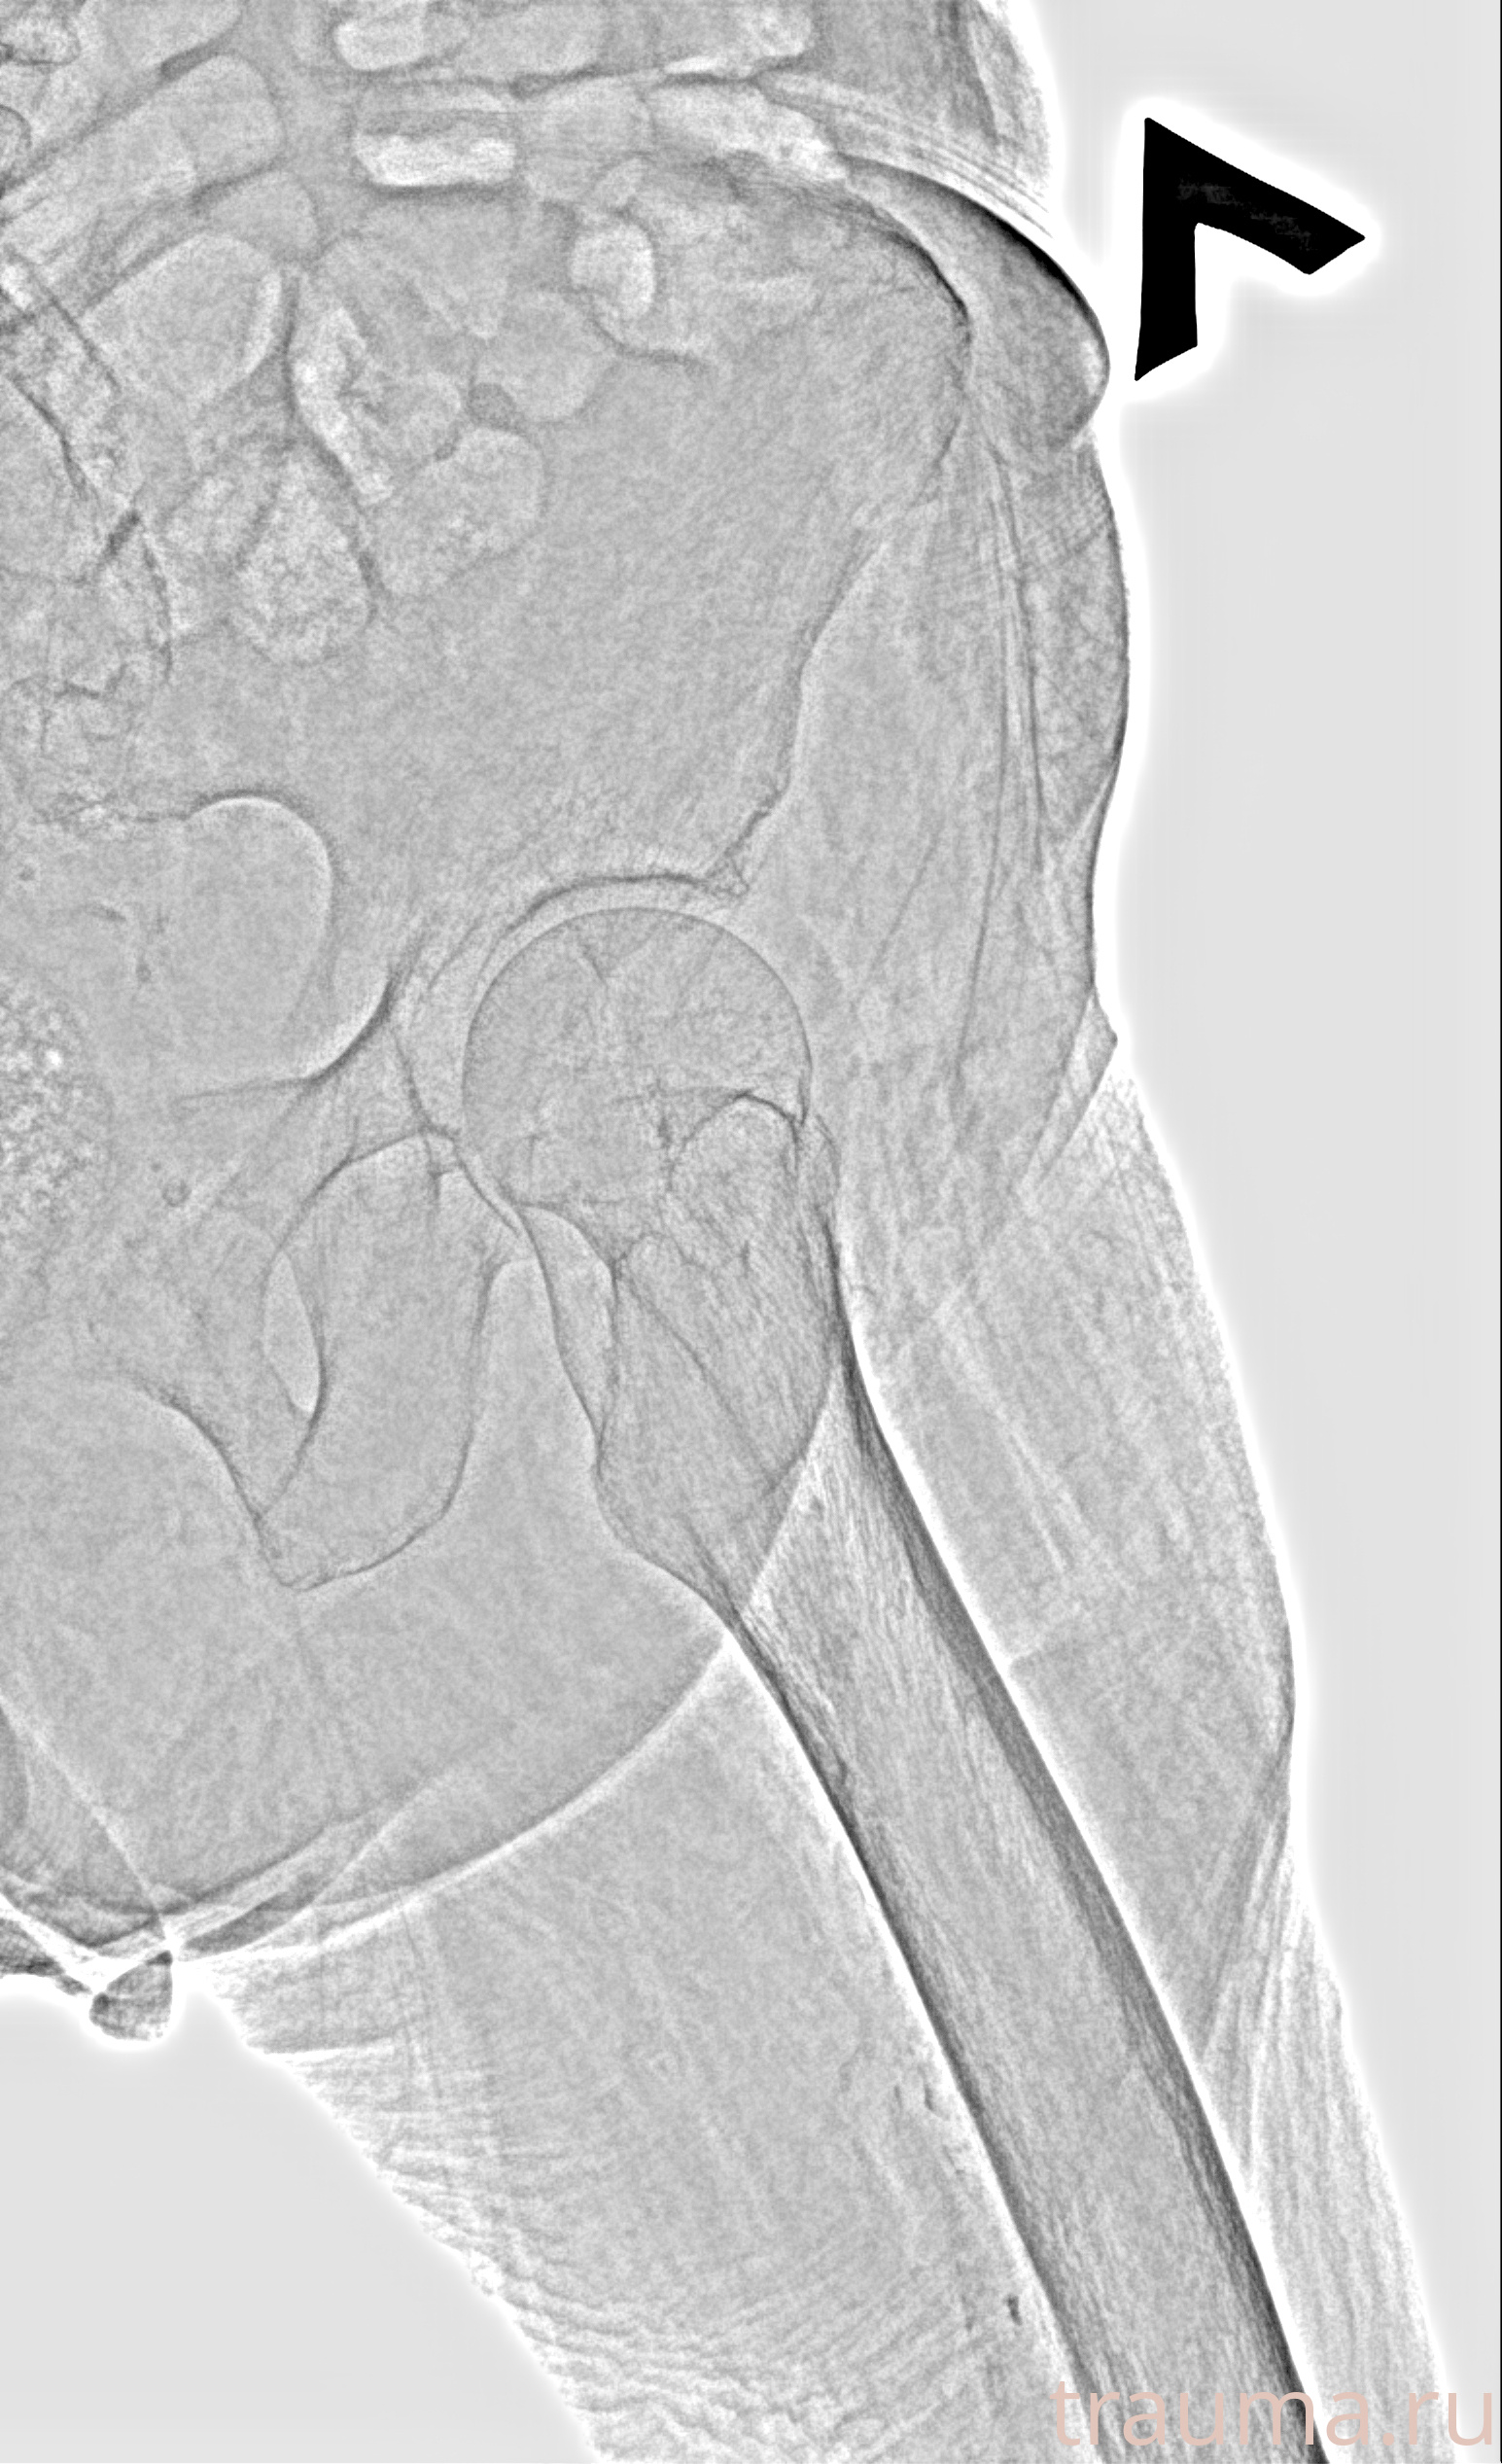

Рентген на дому: по вашему адресу приезжает врач-рентгенолог, травматолог-ортопед с мобильным рентгеновским аппаратом, проводит диагностику травмы или заболевания, делает необходимые рентгенограммы, дает рекомендации по дальнейшему лечению. Получить качественные снимки в домашних условиях возможно благодаря уникальной методике, разработанной МосРентген Центром для института  Склифосовского